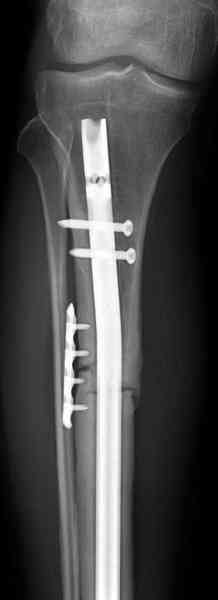

conference мы разбирали похожий случай, ложный сустав большеберцовой кости после резекции опухоли.

Оперирован в военном госпитале с заменой сегмента

аллокостью большеберцовой кости и после демобилизации явился для постоянного наблюдения по месту жительства.

Наши имели проблему со сращением, пришлось им сделать динамизацию, дополнительную аутопластику.

Снимки представлены.